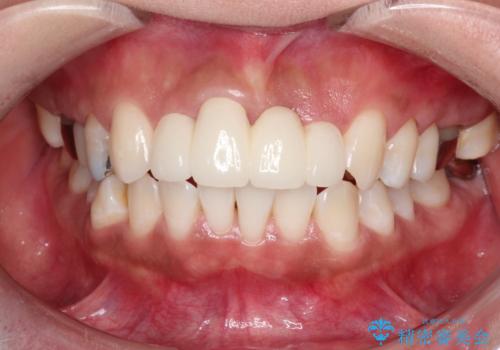

仮歯に変えた時点で臭いや色などが改善され、気に入っていただけました。

被せ物はなるべく白くしたいとの事で、ホワイトニングも行い綺麗に仕上がり、患者様は大変満足されました。